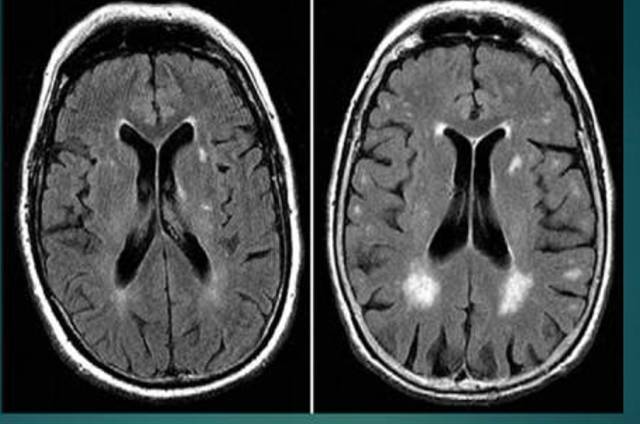

脑白质脱髓鞘

脑白质脱髓鞘,脑白质位置

脑白质脱髓鞘改变

缺血性脑白质病变

脑白质脱髓鞘病变

脑白质病变

脑白质疏松

脑白质高信号